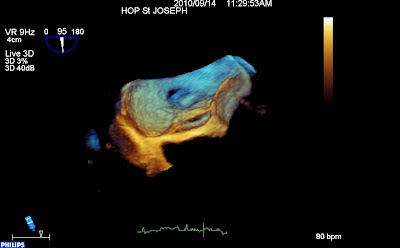

L’accolement des parties du SIA n’est pas fixe, comme ne témoigne cette vue « en face »du FOP, avec une fente laissant libre passage de l’OD (en dessous) vers l’OG (au dessus).